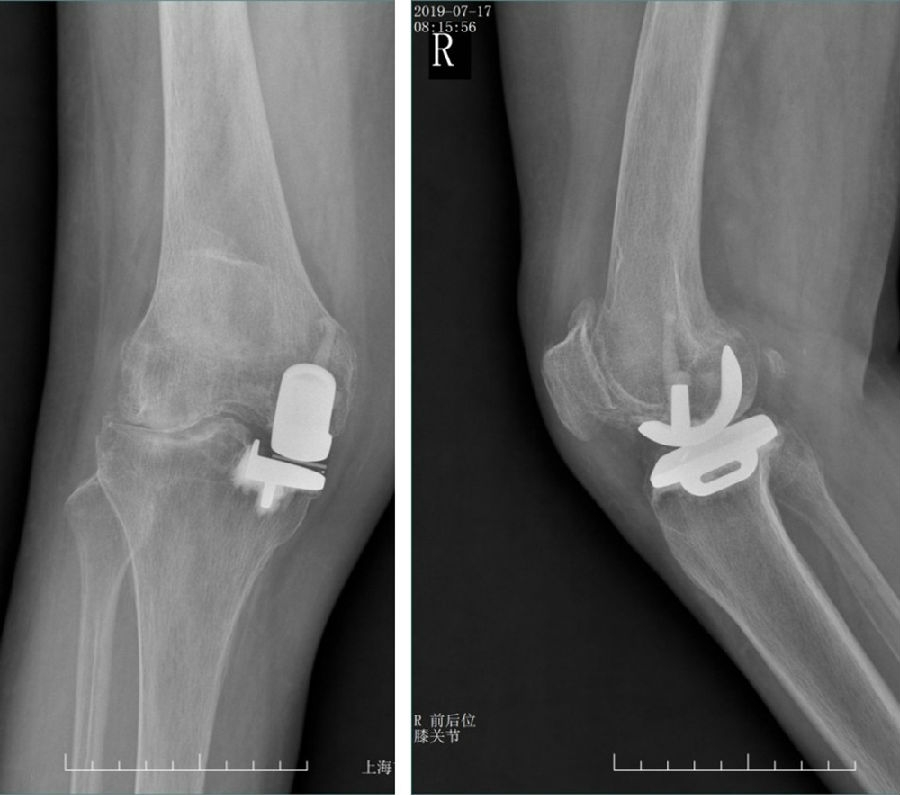

Case3:一期Bi-UKA治疗双间室OA

术前动力位片

术前透视。A.模拟负重位B.内翻应力位C.外翻应力位D.侧位

术后透视。A.正位B.侧位

术后1X-ray